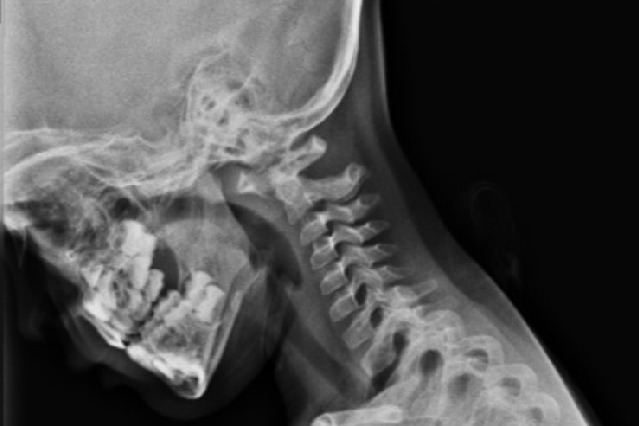

చివరకు ఆమె ఎముకను ఫిక్స్ చేయడానికి హెర్బెర్ట్ స్క్రూలు అనే చిన్న స్క్రూలను ఉపయోగించి శస్త్రచికిత్స చేయాలని నిర్ణయించాం. అందులో అత్యంత చిన్నవి 20 మిల్లీమీటర్ల పొడవు, 2.4 మిల్లీమీటర్ల వ్యాసంలో ఉన్నాయి. సీటీ స్కాన్లో పరిశీలిస్తే, బాలిక సి2 ఇస్త్మస్ 2.6 మిల్లీమీటర్ల వ్యాసం (మెడకు, వెన్నెముకకు మధ్య), పొడవు 20 నుంచి 24 మిల్లీమీటర్లు ఉన్నట్లుతెలిసింది. దాంతో ఆ స్క్రూలను ఉపయోగించి, చిన్న ఎముకలను సరిచేయాలని నిర్ణయించాం. అయితే, అప్పటికే ఇన్ఫెక్షన్ వ్యాపించి, ఎముకలు తీవ్రంగా దెబ్బతినడంతో, జాయింటును అతికించడానికి అక్కడ తగినంతగా ఎముకలు లేవు. దాంతో ఆమె తల్లి కటి ప్రాంతంలోని ఎముకను తీసి పాపకు అమర్చాలని భావించాం.

ఎట్టకేలకు శస్త్రచికిత్సకు అన్నీ సిద్ధం చేశాం. ముందుగా తల్లి కటి ప్రాంతం నుంచి ఒక ఎముకను తీసి, పాపకు ఇంట్రా ఆపరేటివ్ న్యూరల్ మానిటరింగ్ అమర్చి శస్త్రచికిత్స ప్రారంభించాం. జాయింటులో ఒకవైపు వెన్నెముకకు సంబంధించిన ప్రధాన రక్తనాళం (ఇదే మెదడుకు రక్తాన్ని సరఫరా చేస్తుంది), మరోవైపు వెన్నెముక ఉన్నాయి. 2.4 మిల్లీమీటర్ల హెర్బెర్ట్ స్క్రూ సిస్టంను ఉపయోగించి, వైర్ల సాయంతో స్క్రూను అమర్చి, సి1, సి2 జాయింట్లు రెండింటినీ విజయవంతంగా సరిచేశాం. చుట్టుపక్కల ఉన్న నిర్మాణాలు, అవయవాలు వేటికీ ఎలాంటి గాయాలూ కాలేదు. తొలి ప్రయత్నంలోనే కచ్చితమైన శస్త్రచికిత్స చేయగలిగాం. అట్లాస్ కేబుళ్లను కూడా వెనకవైపు నుంచి ఉపయోగించి, అతికించిన ఎముకను స్థిరంగా ఉండేలా చేశాం. ఫ్యూజన్ను మరింత పెంచేందుకు కృత్రిమ డీఎంబీ, బి-టీపీసీలను కూడా ఉపయోగించాం. శస్త్రచికిత్స అనంతరం తీసిన ఎక్స్-రేలలో అంతా బాగుండటంతో పాపను ఆరు రోజుల తర్వాత ఆస్పత్రి నుంచి డిశ్చార్జి చేశాం.